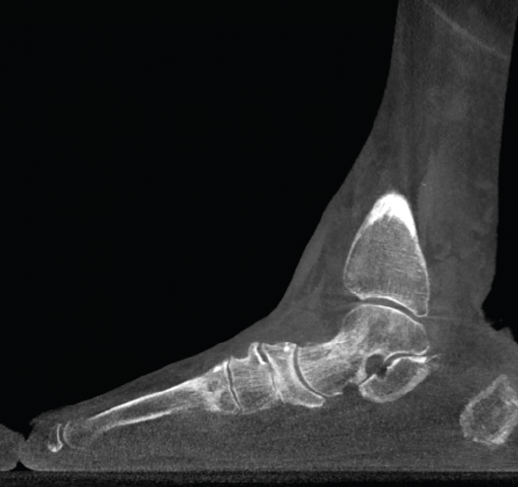

La TAC en carga es una TAC de pequeñas dimensiones que permite un estudio de los 2 pies y tobillos en 360°, con la posibilidad de realizar carga en diferentes posiciones como flexión dorsal forzada, flexión plantar, etc. (Figura 1).

Figura 1. Tomografía axial computarizada en carga de Curve Beam®.

La plataforma de estudio tiene una superficie suficiente para poner los 2 pies en carga con el paciente en bipedestación o incluso de puntillas. También existe la posibilidad de usar diferentes tipos de zapatos o plantillas en el estudio para estudiar las correcciones.

La irradiación es mucho menor que la de una TAC convencional, un aspecto similar a lo que vemos en los miniarcos en C de quirófano si los comparamos con un arco normal. El tiempo de estudio es muy rápido.